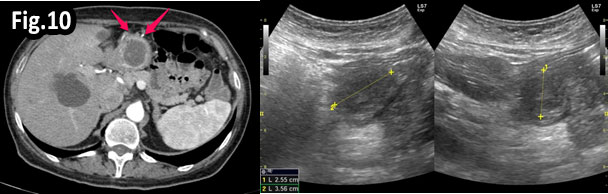

GISTs are rare mesenchymal neoplasms of the digestive tract [1,2]. They have been documented in all parts of the gastrointestinal tract, but are most common in the stomach and small intestine, followed by colo-rectum, mesentery, and esophagus [1,2]. However, the synchronous occurrence of lung cancer and GIST is extremely rare [3]. The incidence of GIST coexisting with additional malignancies is 9% to 27%, and primary lung cancer in GIST patients is 0.5%-1.2% [3]. A 75 year old woman with a smoking history for >30 years was diagnosed with advanced stage of left lung primary adenocarcinoma by chest computed tomography (CT) and bronchoscopy with sampling in February 2015 (Fig.1, Fig.2). The patient started Erlotinib 150 mg/day. In September 2015 the patient was admitted with vague abdominal pain and postprandial vomiting. Physical examination, routine blood, urine and stool investigations were unremarkable. Abdominal ultrasound detected an oval, homogenous, hypoechoic lesion 6/5/4 cm, arising from the submucosal layers of the gastric wall (Fig 3). The color Doppler demonstrated neovascularization (Fig 4). Except for 3 small simple liver cysts, no other abnormalities were present. Upper endoscopy and endoscopic ultrasound (EUS) revealed a large oval, slightly lobulated mass, hypoechoic 6x5cm between incisura angulars and greater curvature of the gastric body, originating from the 4th layer of the wall (muscularis propria). The tumor was slightly “dumbbell” shaped, protruding in and outside the stomach lumen, with several irregular hypoechoic zones and micro cysts within, looked encapsulated without infiltration of the surrounding tissues and pathologic abdominal lymph nodes (Fig. 5). A contrast-enhanced ulstrasound (CEUS) and contrast-enhanced computed tomography (CECT) of the abdomen additionally characterized the lesion and excluded liver metastases. (Fig. 6, Fig. 7) Percutaneous true-cut biopsy of the lesion was performed (18G, two separate puncture sites) (Fig 8). The immunohistochemical analysis revealed epithelioid-type GIST, diffusely positive for c-kit (CD117), with a weak focal expression of S-100 (Fig. 9). Due to life expectancy defined by the unresectable advanced lung cancer, the patient was not indicated for resection of the gastric GIST. Imatinib (Glivec) 400 mg/day was started as a “co-therapy” to Erlotinib in November 2015. After 12 months of co-treatment, a good control of both tumors was achieved. CT and abdominal ultrasound showed the gastric lesion was slightly shrunk on therapy, with large central necrosis (Fig. 10). The patient is being followed up.

Figure 10: CT and US at 12 month follow-up: Reduced lesion size and central necrosis.